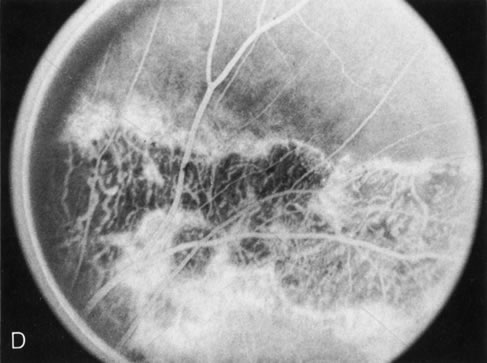

HEREDITARY HEMORRHAGIC MACULAR DYSTROPHY (PSEUDOINFLAMMATORY MACULAR DYSTROPHY OF SORSBY)

FA plays an important role in the understanding of this rare disorder. In the earliest manifestations of the disease, FA shows a single, isolated choroidal neovascular membrane unassociated with other causes of a membrane, such as drusen or angioid streaks (Fig. 13).25 Presumably this membrane is the cause of the subsequent hemorrhagic maculopathy with secondary disciform scarring, occurring initially in the macula but often extending throughout the retina.

Fig. 13. Hereditary hemorrhagic macular dystrophy (pseudoinflammatory macular dystrophy of Sorsby). Fluorescein angiography in this family member demonstrates that the earliest finding is an isolated choroidal neovascular membrane B). Despite laser photocoagulation, a hemorrhagic maculopathy developed in this eye (C, D) and eventually a disciform scar (E) formed, as it had in the fellow eye, and in the eyes of other affected family members.

Abnormal choroidal perfusion, manifested on FA as a delay in choriocapillaris filling, has been seen in the restudy of some of Sorsby's initial pedigrees.26 This unusual pattern has been related to the histopathologic finding of a “confluent, lipid-containing, amorphous deposit found between the basement membrane of the RPE and the inner collagenous layer of Bruch's membrane.”27